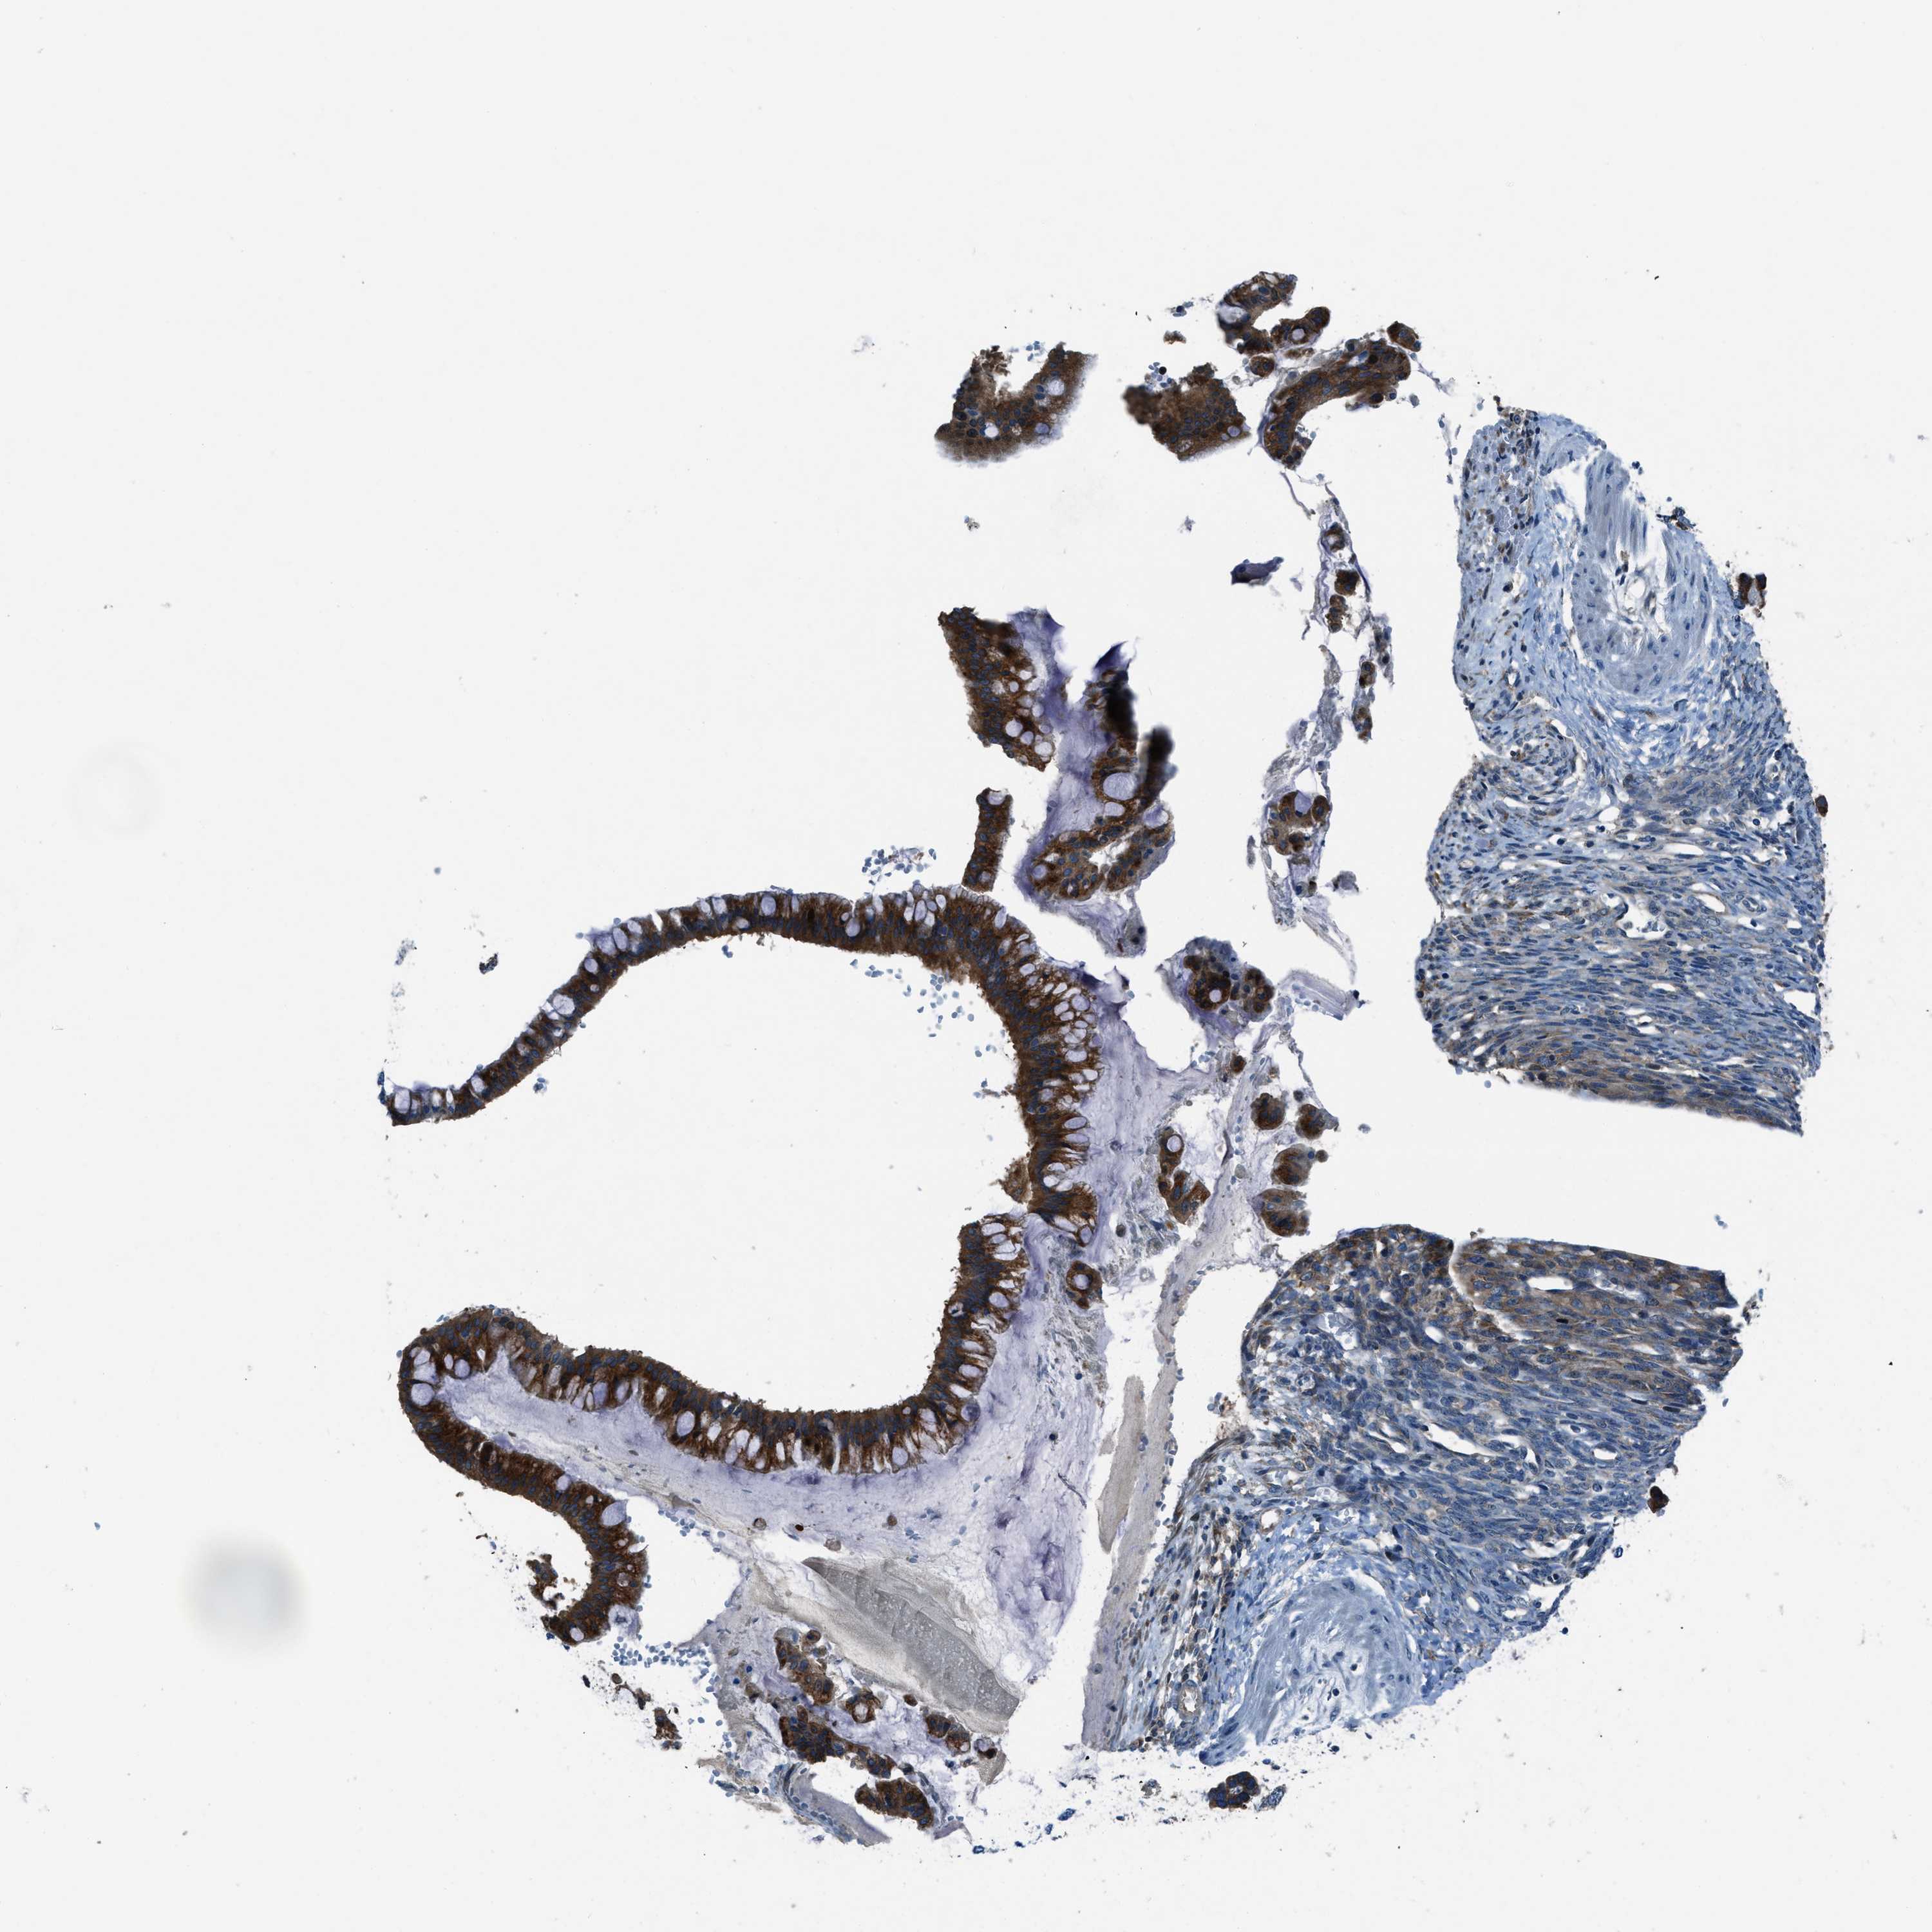

OVARIAN CANCER - Protein expressioni

A mouse-over function shows sample information and annotation data. Click on an image to view it in a full screen mode. Samples can be filtered based on level of antibody staining by selecting one or several of the following categories: high, medium, low and not detected. The assay and annotation is described here.

Note that samples used for immunohistochemistry by the Human Protein Atlas do not correspond to samples in the TCGA dataset.

Antibody stainingi

Antibody staining in the annotated cell types in the current human tissue is reported as not detected, low, medium, or high, based on conventional immunohistochemistry profiling in selected tissues. This score is based on the combination of the staining intensity and fraction of stained cells.

Each image is clickable and will lead to virtual microscopy that enables deeper exploration of all samples and also displays staining intensity scores, fraction scores and subcellular localization as well as patient and tissue information for each sample.

Antibody HPA016649

Antibody HPA018152

Cystadenocarcinoma, serous, NOS

Carcinoma, endometroid

Cystadenocarcinoma, mucinous, NOS

Carcinoma, NOS